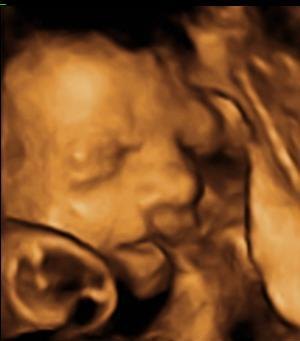

Ser frem til at læse om din scanning